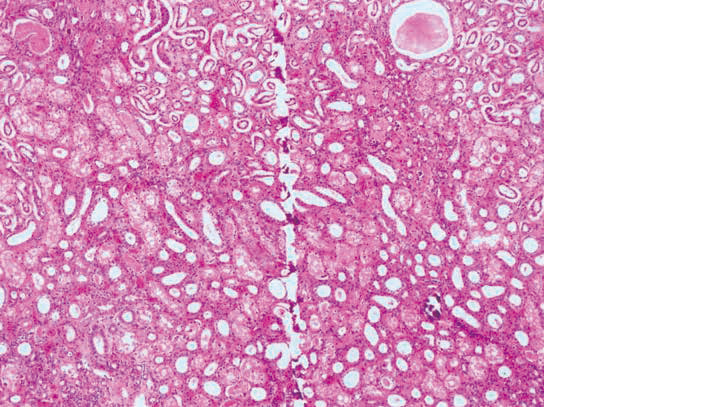

H-E染色標本を示す。

不良標本となった原因として考えられるのはどれか。

2つ選べ

。

1. 組織片に石灰化がある。

2. ミクロトーム刃に傷がある。

3. ミクロトームの滑走路が錆びている。

4. ミクロトーム刃の固定が不完全である。

5. パラフィンの浸透時間が不足している。